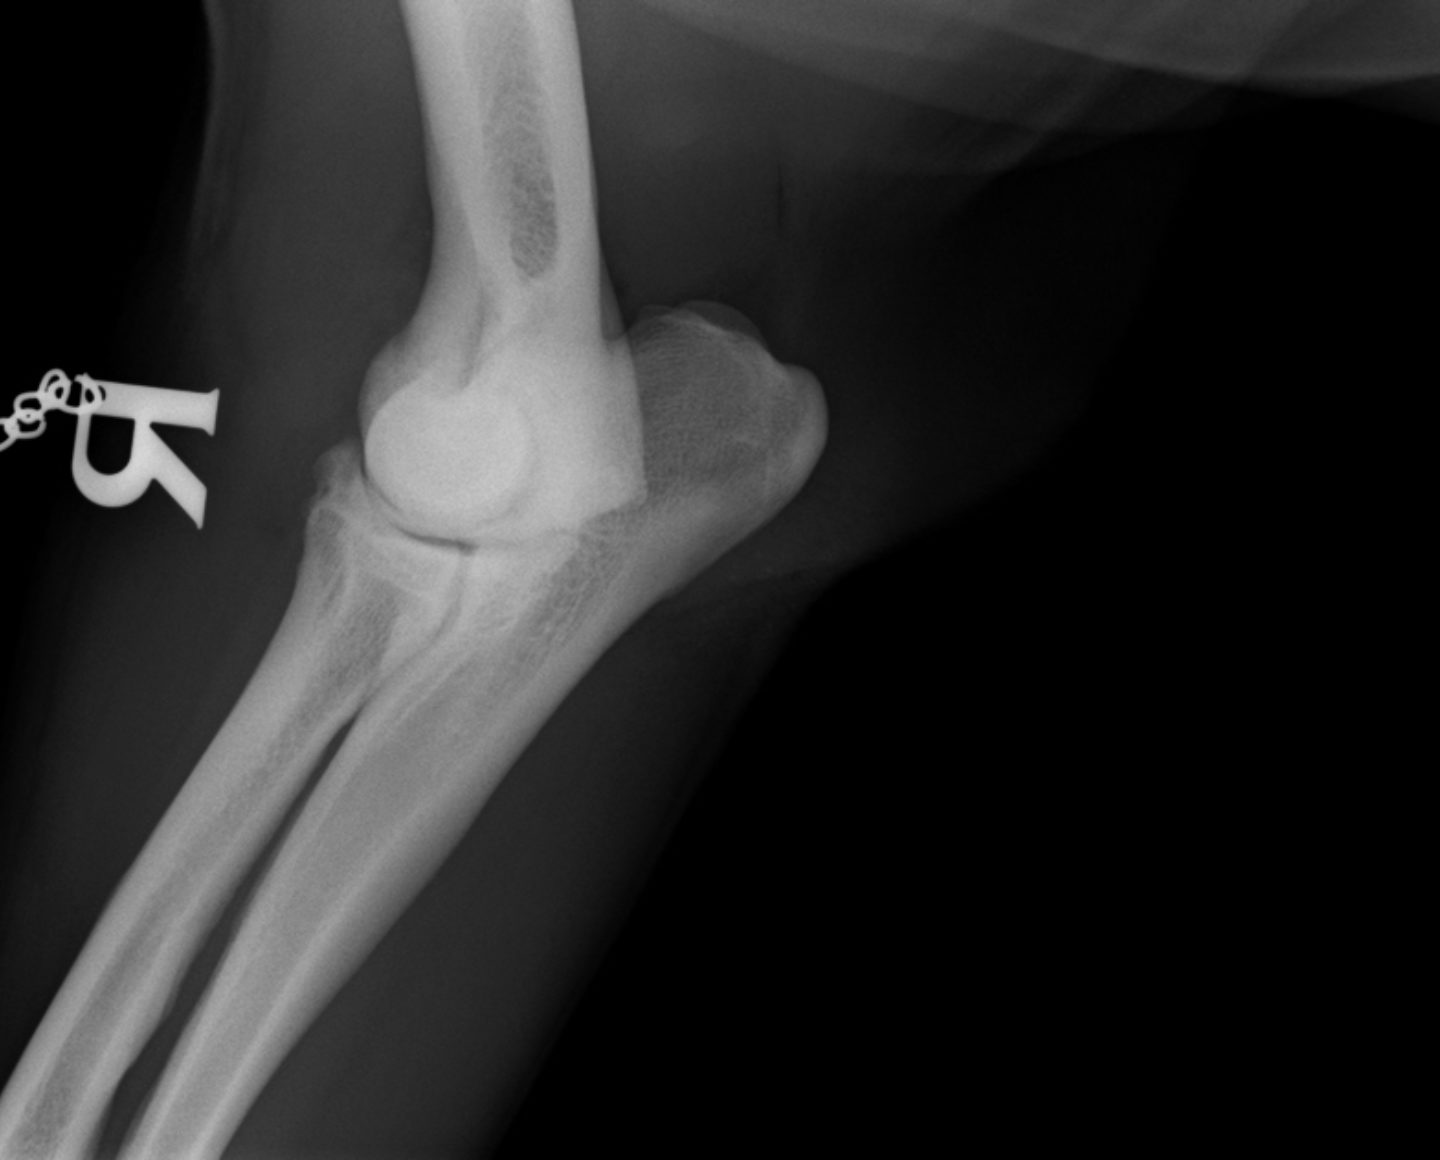

Im August 2013 wurde ein acht Jahre alter männlich kastrierter Labrador mit beidseitig hochgradiger  Ellenbogengelenksarthrose vorgestellt. Der Hund war beidseits wegen eines frakturierten Processus Coronoideus (Der Proccesus Coronoideus stellt einen wichtigen knöchernen Stabilisator des Ellenbogengelenks dar) operiert, einseitig nachoperiert und auf beiden Seiten mehrfach mit Cortison-Injektionen behandelt worden.